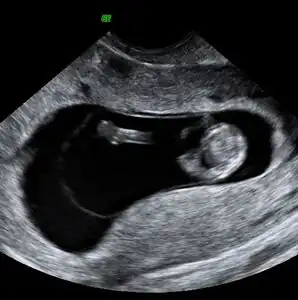

Obstetric ultrasonography may also be used to detect and diagnose pregnancy. It is very common to have a positive at home urine pregnancy test before an ultrasound. Both abdominal and vaginal ultrasound may be used, but vaginal ultrasound allows for earlier visualization of the pregnancy. With obstetric ultrasonography the gestational sac (intrauterine fluid collection) can be visualized at 4.5 to 5 weeks gestation, the yolk sac at 5 to 6 weeks gestation, and fetal pole at 5.5 to 6 weeks gestation. Ultrasound is used to diagnose multiple gestation.[3][19]

-

Ultrasound: early pregnancy -

Ultrasound: failed early pregnancy

Ultrasound is also a common tool for determining viability and location of a pregnancy. Serial ultrasound may be used to identify non-viable pregnancies, as pregnancies that do not grow in size or develop expected structural findings on repeated ultrasounds over a 1-2 week interval may be identified as abnormal.[34] Occasionally, a single ultrasound may be used to identify a pregnancy as non-viable; for example, an embryo that is greater than a certain size but that lacks a visible heart beat may be confidently determined to be not viable without the need for follow up ultrasound for confirmation.[34]